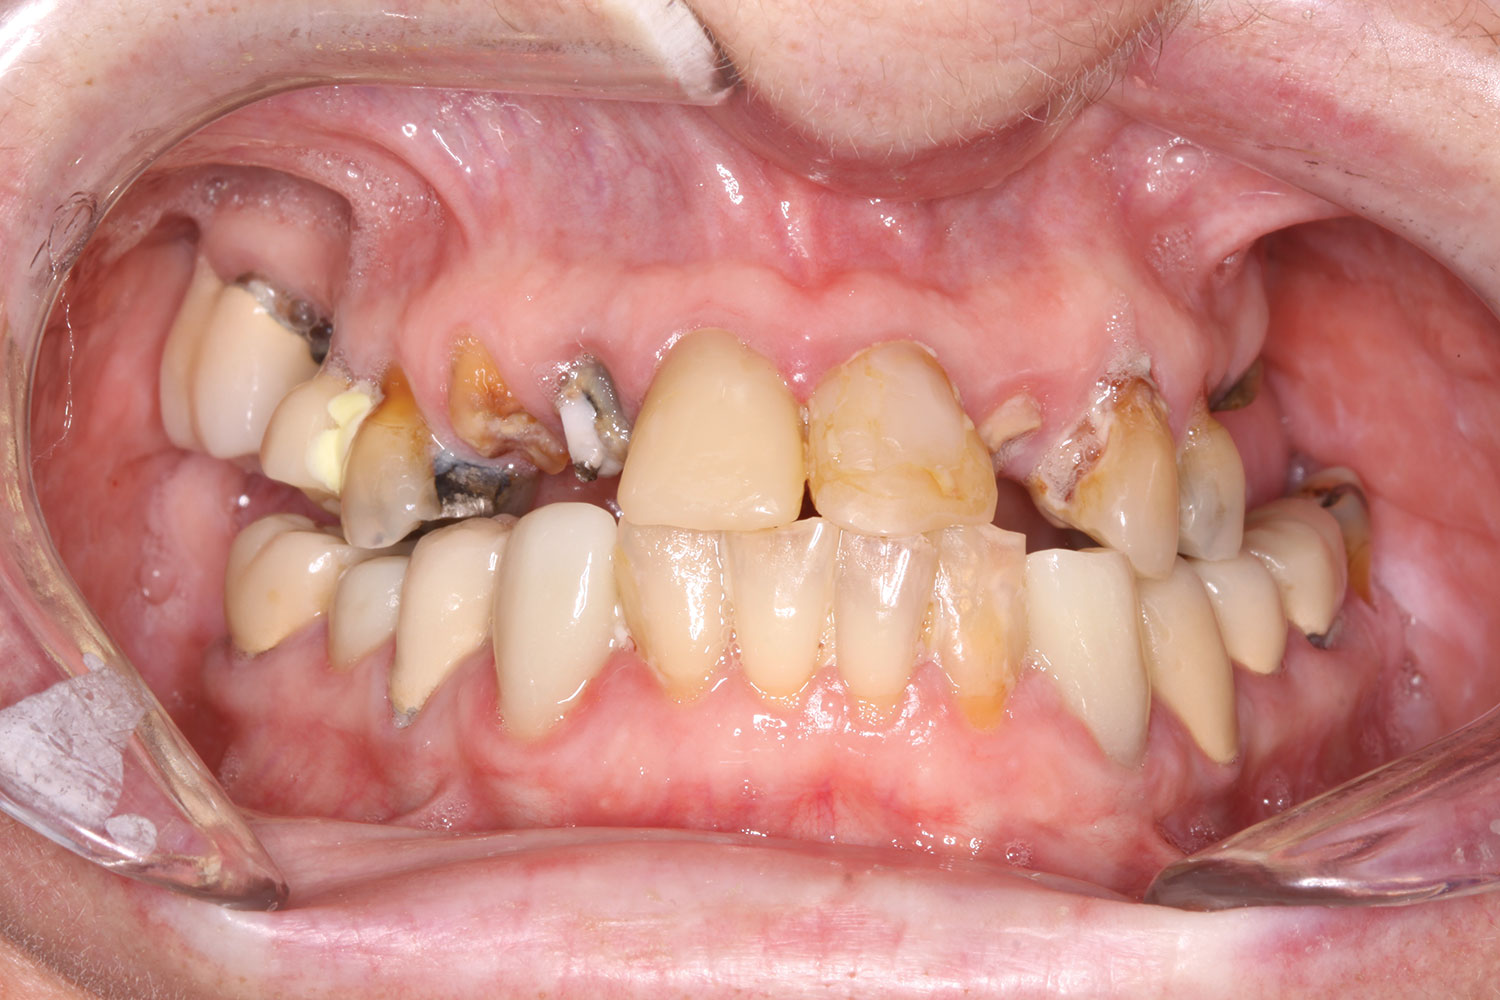

Fig 10. Initial clinical situation, intraoral view.

Figure 10

A 60-year-old female patient presented with many periodontally and restoratively hopeless teeth that severely compromised esthetics and function and were inadequate to retain a maxillary restoration. She declined to advance into a full maxillary denture or partial denture. Existing maxillary teeth included Nos. 2 and 4 through 14 (Figure 9 and Figure 10). The opposing dentition was stable. The patient was in good health with no allergies to medication.